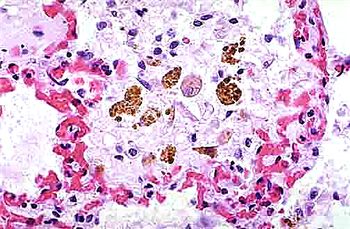

在腫瘤微環(huán)境中,巨噬細胞被募集并分化為腫瘤相關(guān)巨噬細胞(Tumor-Associated Macrophages, TAMs)。TAMs在腫瘤的生長、侵襲、轉(zhuǎn)移及血管生成等方面發(fā)揮重要作用。它們可以通過分泌多種細胞因子和生長因子,促進腫瘤細胞的增殖和遷移,并抑制抗腫瘤免疫反應。因此,靶向TAMs的腫瘤免疫療法成為當前腫瘤治療領(lǐng)域的研究熱點。

圖4